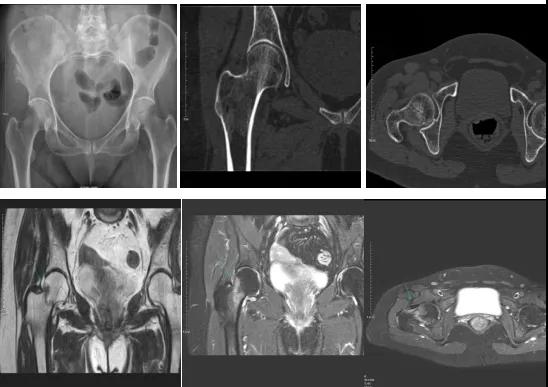

DR示:右側(cè)股骨頸未見明顯骨折征象。CT右側(cè)股骨頸骨質(zhì)密度不均?;颊唧w征明顯,為明確診斷,行MRI檢查。MRI示:右側(cè)股骨頸T1WI呈低信號,脂肪抑制序列呈高信號;提示右側(cè)股骨頸隱匿性骨折。